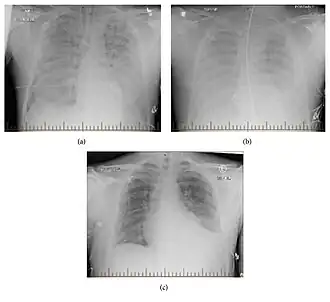

Radiographic progression of hantavirus pulmonary syndrome in patient.

Molecular Diagnostic Techniques

Diagnosis primarily relies on molecular methods, such as reverse transcription-polymerase chain reaction (RT-PCR), which can detect hantavirus RNA in blood or tissue samples.[12] Molecular diagnostics are essential due to BAYV's genetic similarity to other hantaviruses, which makes serological distinction challenging. Additionally, the early symptoms of HPS are non-specific and general, making the genetic diagnostic techniques even more critical.[12]